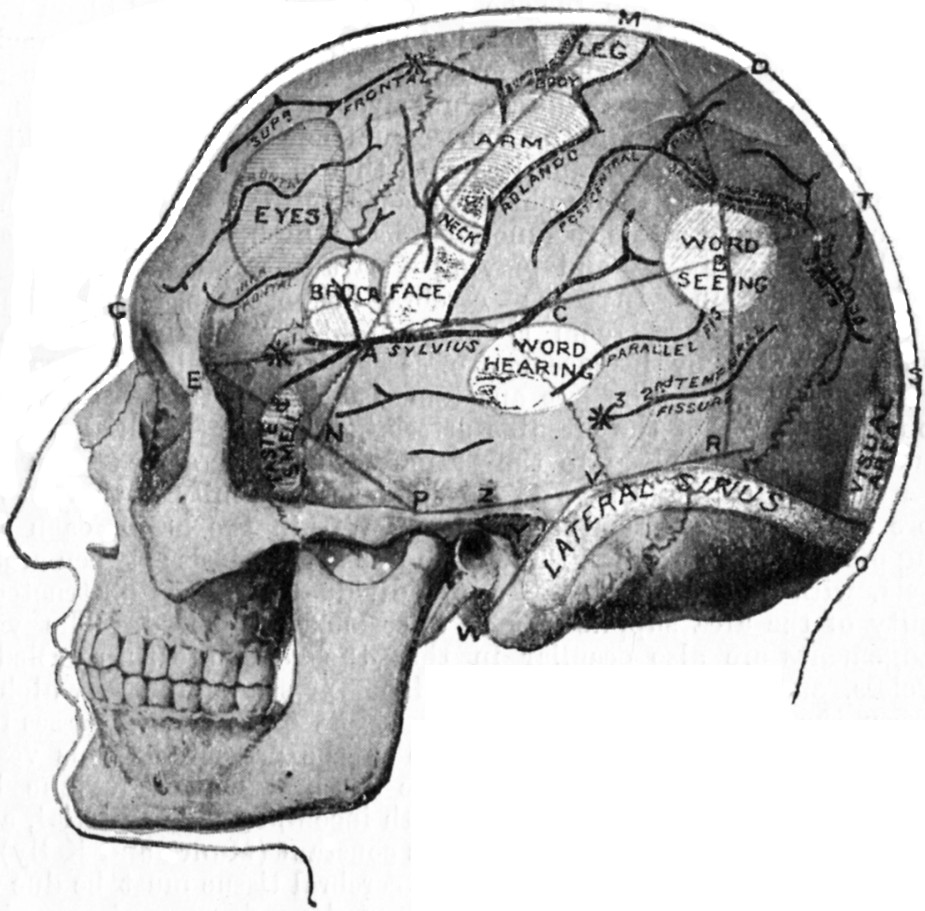

179.Relations of the Motor and Sensory Areas to the Convolutions and to Chiene's Lines330

181.Chiene's Method of Cerebral Localisation336

182.To illustrate the Site of Various Operations on the Skull337